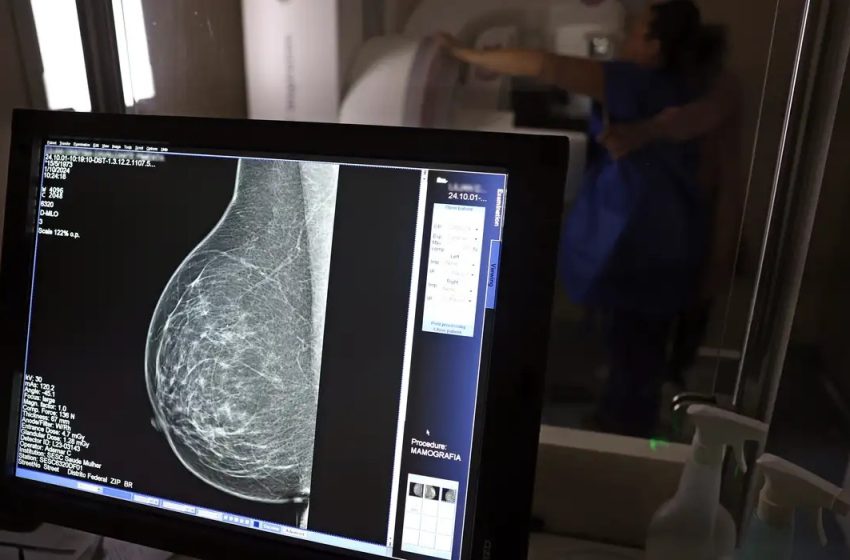

Falta de acesso a mamógrafos limita prevenção do câncer de mama

No mês de conscientização sobre o câncer de mama, um relatório destaca a importância de acesso igualitário ao rastreamento e tratamento da doença. Segundo o Atlas da Radiologia no Brasil, do Colégio Brasileiro de Radiologia e Diagnóstico por Imagem (CBR), o acesso aos mamógrafos ainda é um desafio.

O país tem 6.826 equipamentos registrados, sendo 96% em funcionamento. Metade deles está disponível no Sistema Único de Saúde (SUS), responsável por atender 75% da população. Isso equivale a 2,13 mamógrafos por 100 mil habitantes dependentes do SUS.

Na saúde suplementar, que cobre 25% da população, o cenário é mais favorável: 6,54 aparelhos por 100 mil beneficiárias, quase o triplo da rede pública. O Acre exemplifica essa disparidade — são 35,38 mamógrafos por 100 mil habitantes na rede privada, contra 0,84 no SUS.

O Brasil tem uma cobertura muito baixa de mamografias: 24%. O ideal recomendado pela Organização Mundial da Saúde é de 70%. Mesmo em lugares como o estado de São Paulo, que tem a maior concentração de mamógrafos do país, a taxa gira em torno de 26%.

Em setembro, o Ministério da Saúde ampliou as diretrizes de rastreamento, recomendando que mulheres entre 40 e 49 anos realizem mamografias, mesmo sem sintomas. De acordo com o Instituto Nacional do Câncer (Imca), mais de 73 mil mulheres recebem o diagnóstico de câncer de mama anualmente no Brasil.